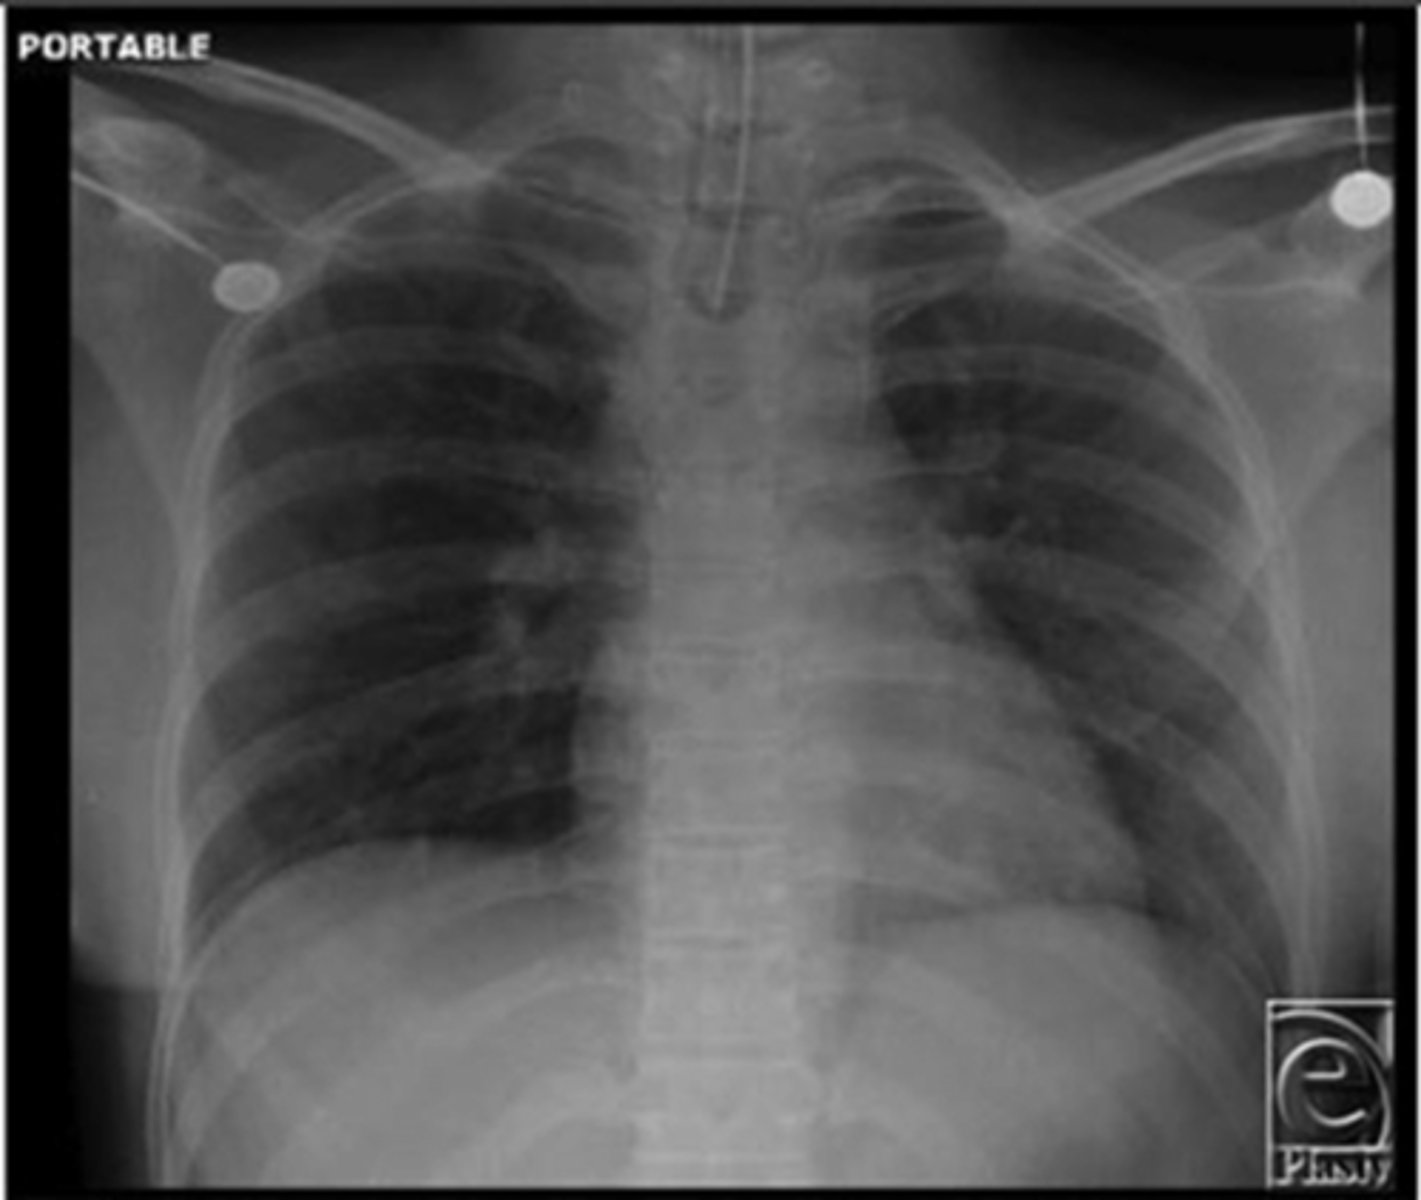

Is this a high-quality film?

Left lung

Where is the abnormality located in the chest?

Atelectasis

What is the red arrow indicating?

Effusion

What is the likely interpretation?